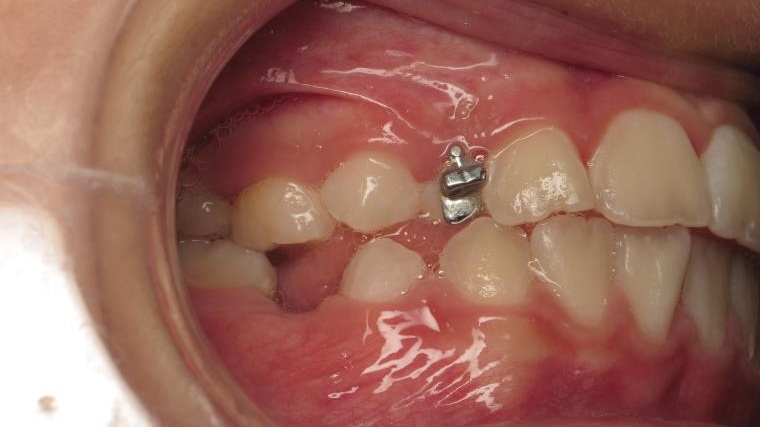

appareillage mobile pendant 9 mois

sectionnel multibagues pendant 25 mois